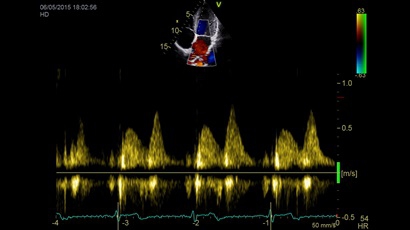

Тканевой допплер:

Да

Направленный энергетический допплер:

Цветовой допплер:

Импульсно-волновой допплер:

• Режимы: 4D, 2D (B-режим), цветной допплеровский режим, режим энергетического допплера, M-режим, цветной M-режим, спектральные режимы импульсно-волнового допплера (PW) и непрерывно-волнового допплера (CW), визуализация скорости движения тканей.